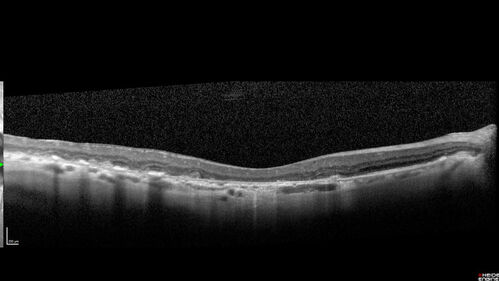

Age-related macular degeneration - Geographic Atrophy - Intermittent CME left eye from CRVO, Anemia, Diabetes

79 year old female - 3 years post CRVO in the left eye (20/32 VA) with intermittent CME.  Left eye is the better eye.  Vision is stable since 2 years ago

PMHx: Type II DM x 20 years, Chronic Anemia, Hyperlipidemia

VA 20/200 OD, 20/50 OS (usually 20/40)